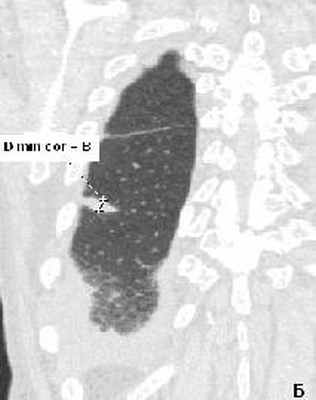

Рис. 2(А, Б). КТ грудной клетки больной Д., 80 лет. Организующая пневмония на фоне десквамативной интерстициальной пневмонии.

А - аксиальный срез на уровне нижних долей легких, выявлены участки диффузного снижения пневматизации по типу «матового стекла», в нижней доле справа выявлена субплевральная консолидация неправильной округлой формы. Б - МПР правого легкого в коронарной проекции на уровне консолидации. Рассчитанное значение 3 D – коэффициента составило 3.43 ( D max axial / D min cor = А/В =3.43), свидетельствующее в пользу доброкачественности консолидации. При трансторакальной биопсии консолидации получены клетки воспаления (макрофаги, незрелые фибробласты), внутриальвеолярные конгломераты соединительной ткани с лимфоцитарной инфильтрацией.